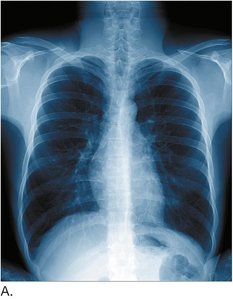

Chest radiography (CXR): X-ray imaging of the lungs

Diseases affecting the lungs include pneumonia, pulmonary edema, pulmonary embolism, tuberculosis, and cystic fibrosis. Pneumonia is an infection of the lung lobes, causing fluid and white blood cells to fill passages. Pulmonary embolism is a blockage of a pulmonary artery by an embolus.